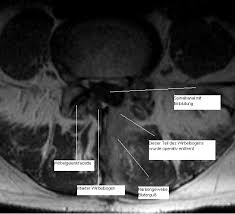

Auf dem MRT erkennt man ein deutliches Narbengewebe. Narbengewebe nach Bandscheiben-OP Zunächst sollte geklärt werden ob die Beschwerden tatsächlich vom Narbengewebe kommen. Habe vor einem Jahr Bandscheiben OP bei L45 mit anschließend 6 Wochen nicht sitzen und darauf 5 Wochen Reha gehabtDie eigentl.

Es kann vorkommen dass nach einer Wirbelsäulen OP Narbengewebe die Nerven bedrängt und das zu erneuten Schmerzen führt. Diese treten typischerweise einige Zeit nach der Operation auf Narben brauchen Zeit sich zu bilden.

Aber dann habe ich Schmerzen wie bei einem BS Vorfall mit starken Schmerzen und ziehen bis in die Wade. Drei Stunden nicht mehr liegen u muß. Diese treten typischerweise einige Zeit nach der Operation auf Narben brauchen Zeit sich zu bilden. Vor 6 Monaten wurde ich an der Bandscheibe L5S1 operiert. Die letzte op ist nun 4 Monate her. Die ideale Narbenpflege nach der OP Aus diesem Grund sollten Sie mit der Narbenbehandlung möglichst bald nach der OP beginnen. Hallo Nach drei BS OPs habe ich nun das Gefühl dass der Nerv durch Narbengewebe bedrängt wird. Hallo wer kann mir etwas zur Bildung von Narbengewebe nach Bandscheiben Operation sagen. Seltener sind Beschwerden nach einer Operation auf die Bildung von Narbengewebe zurückzuführen.

Bei weichem durchlässigem Gewebe kann die Lymphe besser wieder abfließen. Ist nach einem evtl. Wucherndes Narbengewebe ist besonders im Bereich der Wirbelsäule problematisch. Selbst die nach Brustoperationen durch Lymphrückstau entstandenen Schwellungen an den Armen lassen sich beseitigen wenn es gelingt das Narbengewebe durch die spezielle Bindegewebs- Faszienbehandlung der Pohltherapie wieder durchlässiger zu machen. Narbengewebe Nach Bandscheiben Op Entfernen. Letzte Anwendung war ein Epiduroskop mit Katheter leider war diese Anwendung erfolglos. Alle konservativen Versuch sollten vorher durchgeführt werden.